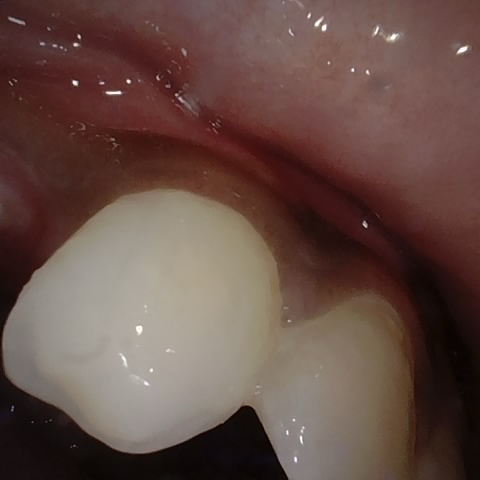

Annotated as "Good"